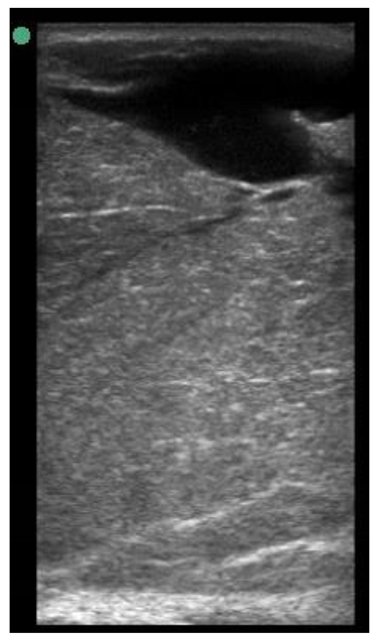

| 109 days of pregnancy (P109) Scanning depth 4.7 cm | ![]() | ![]() | MT generous: 36.8 mm MT conservative: 27.2 mm Gland cistern: 4.7 mm Parenchyma: 15.4 mm Fat Pad: 5.5 mm |